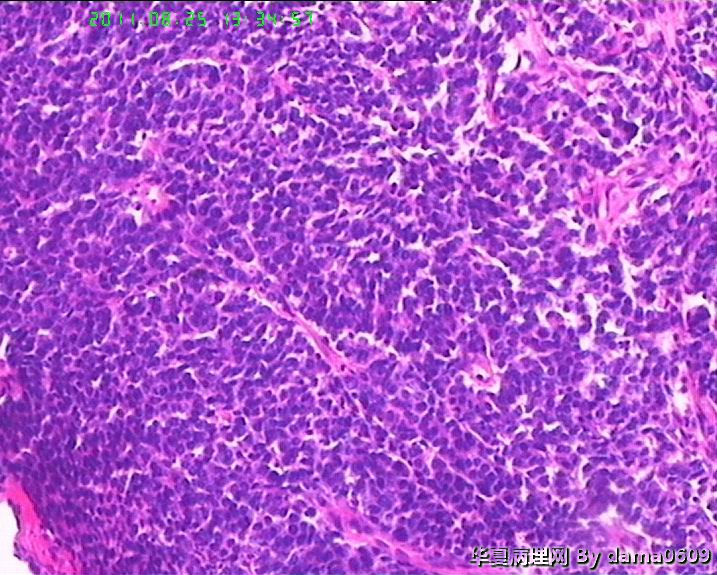

患者男性,39岁。以回盲部肿物行肠镜检查、活检。镜下四块组织内有两块见呈巢状的小细胞(如图

),另两块为粘膜慢性炎表现及坏死组织。学生不知如何分类:未分化癌?类癌?小细胞癌?请老师指教。谢谢!

细胞核较小、深染、一致,核分裂象少见,支持典型类癌。

神经内分泌肿瘤 淋巴瘤 低分化腺癌。。。

神经内分泌肿瘤

楼主是想说“未分化癌”?片子切的比较厚,考虑神经内分泌肿瘤,低分化腺癌待排。

神经内分泌肿瘤?低分化腺癌?标一下神经内分泌标记

高级别癌,活检标本,可做IHC先排除高级别神经内分泌肿瘤。

如果神经内分泌阴性,明确分型等手术根治标本。